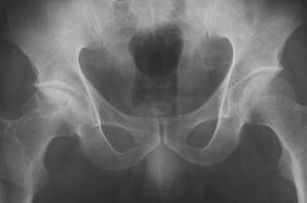

找到骶裂孔,嚴(yán)格消毒鋪孔巾,普魯卡因局部浸潤(rùn)麻醉后,用9號(hào)腰穿針與骶骨成30°~45°角刺入約4.5~5.5cm,拔出針芯如無(wú)腦脊液流出即可注入藥液。注入速度要慢,約2~3min注完。

但最多不超過(guò)5次。穿刺注意事項(xiàng):骶裂孔與珠網(wǎng)膜下腔終端的距離最長(zhǎng)約75mm,最短為19mm,平均約47mm,故穿刺針不要進(jìn)入骶管內(nèi)過(guò)深,以免刺入珠網(wǎng)下腔引起不良后果。

骶管腔容積最小12ml,最大65ml,平均30ml,故注入藥液最大劑量不宜超過(guò)30ml。